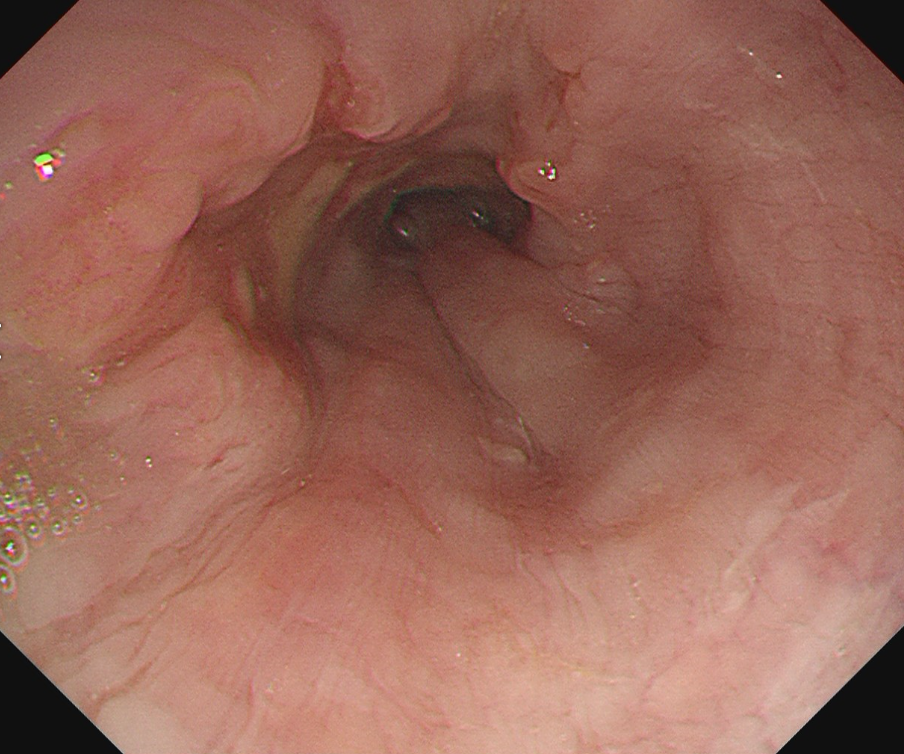

術中内視鏡画像(ダビンチ手術)